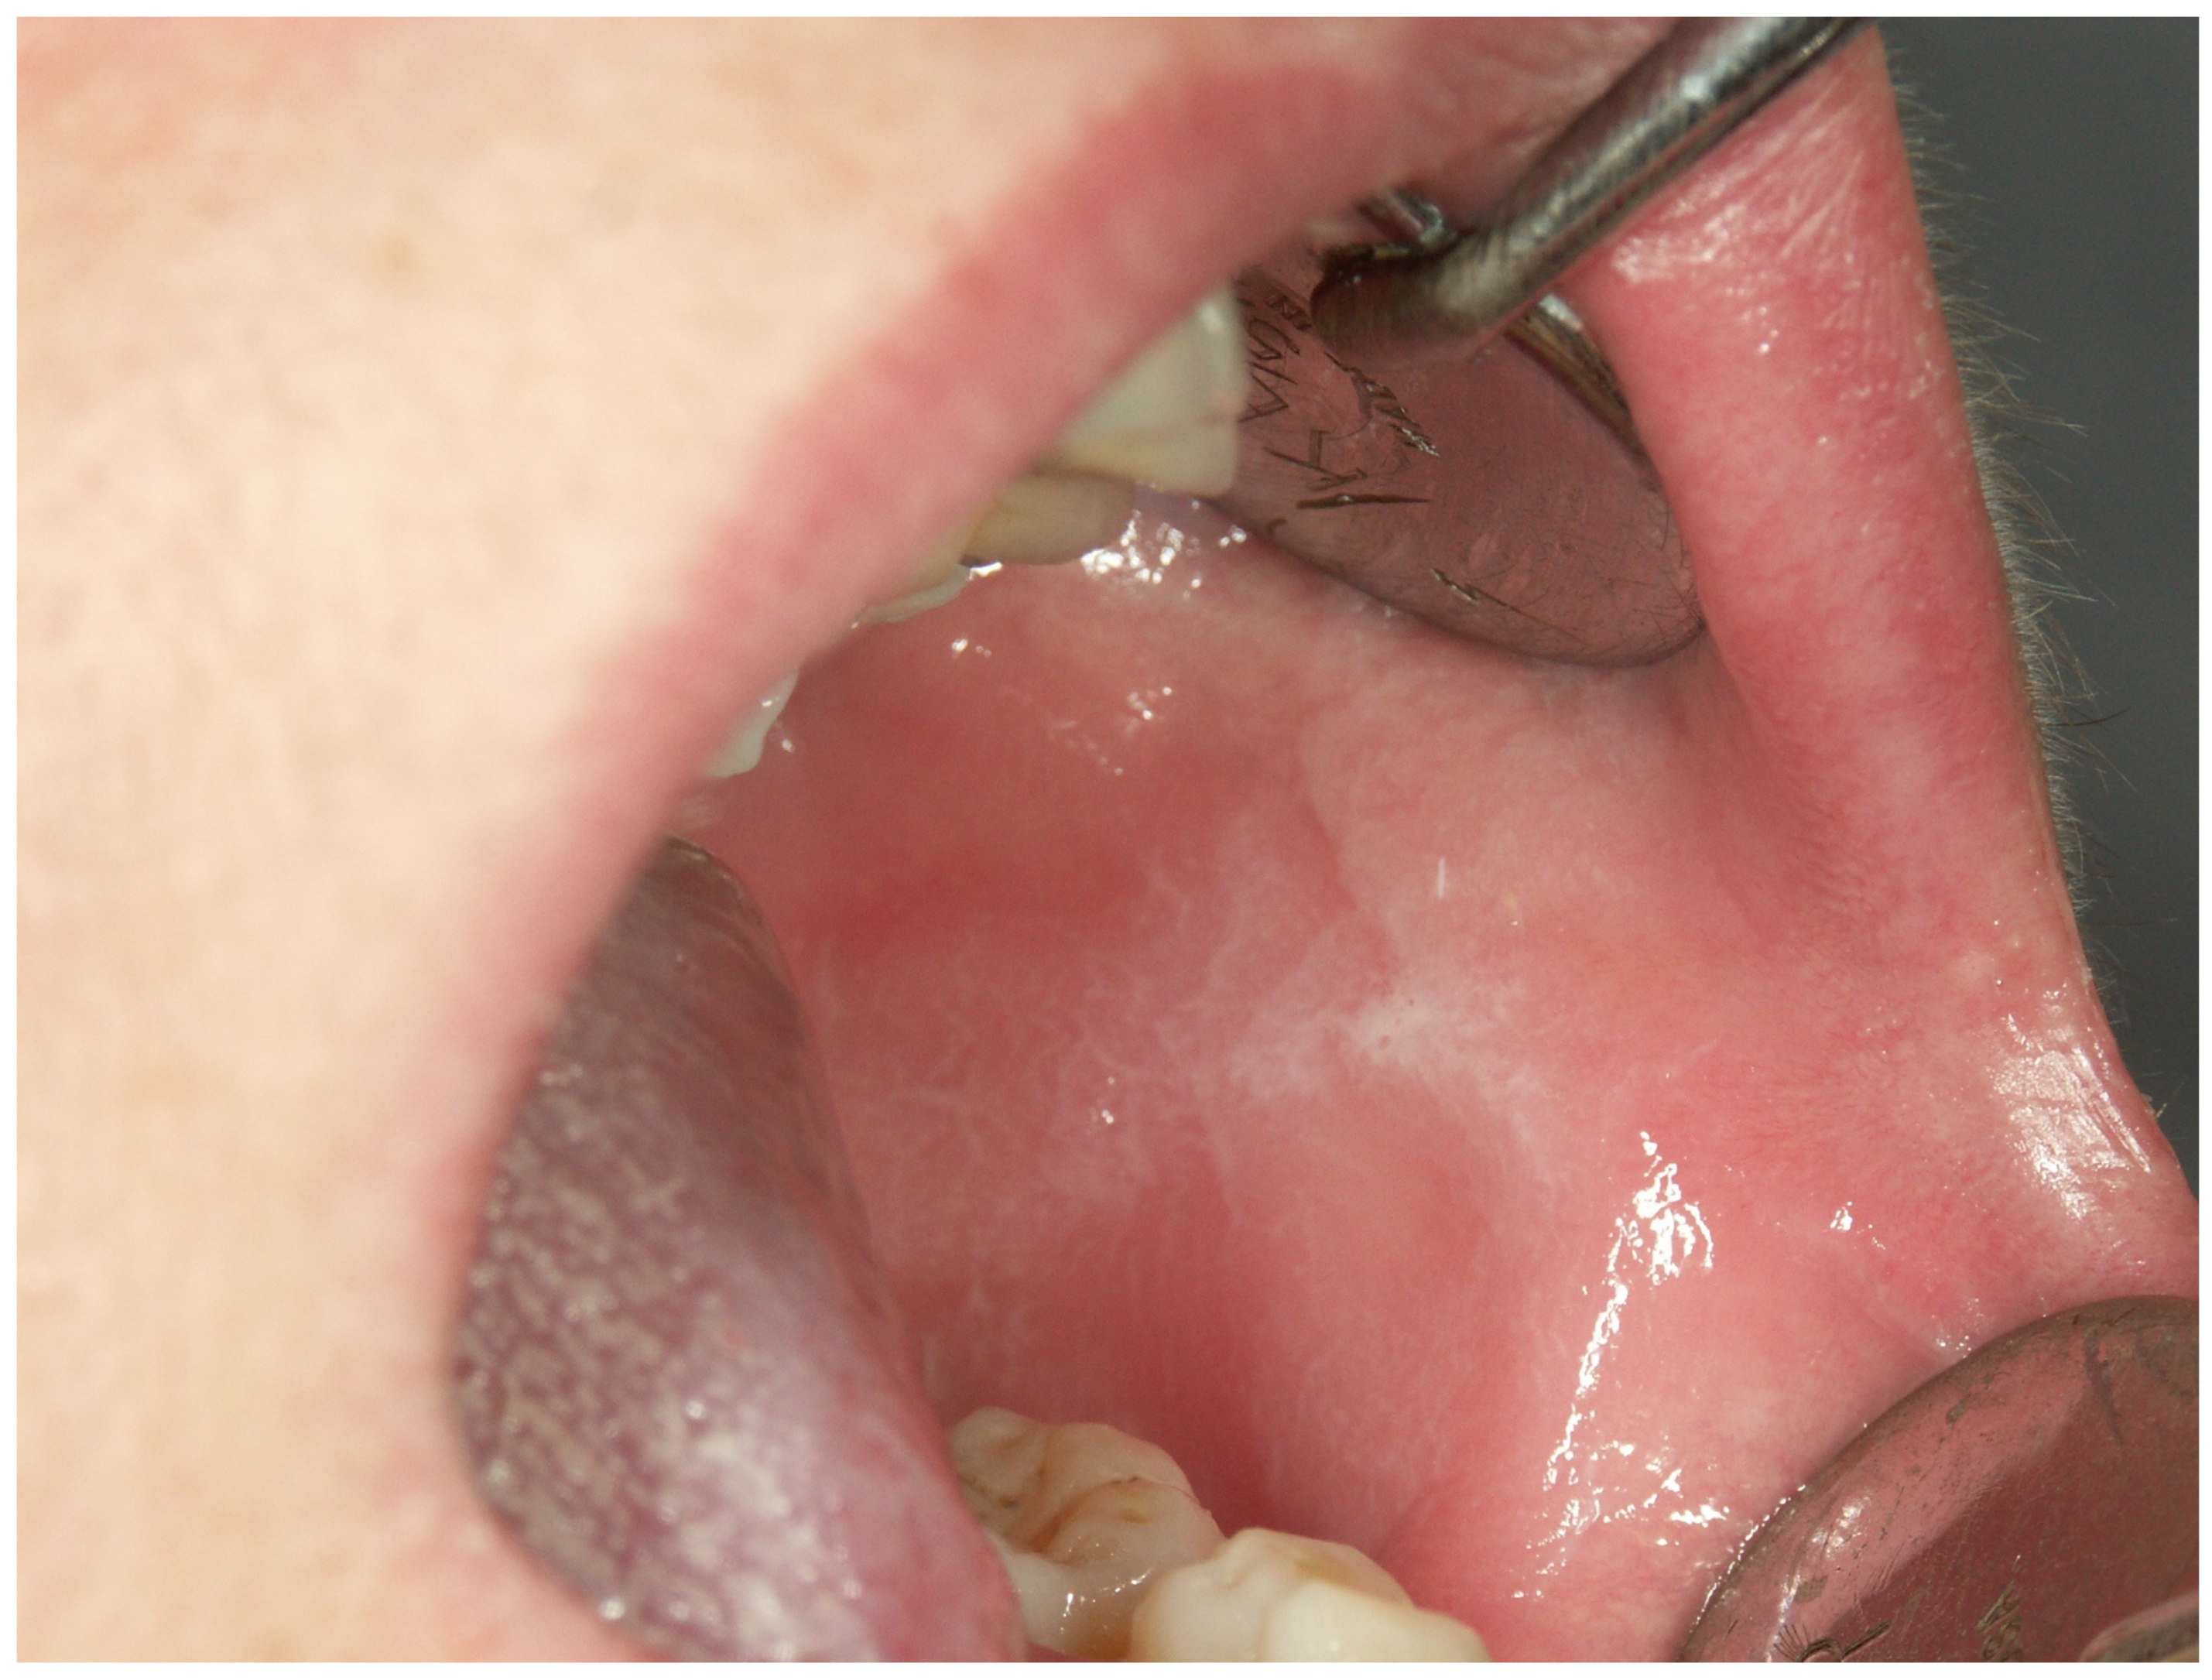

Appendix A. Clinical Presentation of OPMD

General Principles of Treatment of the Main OPMDs